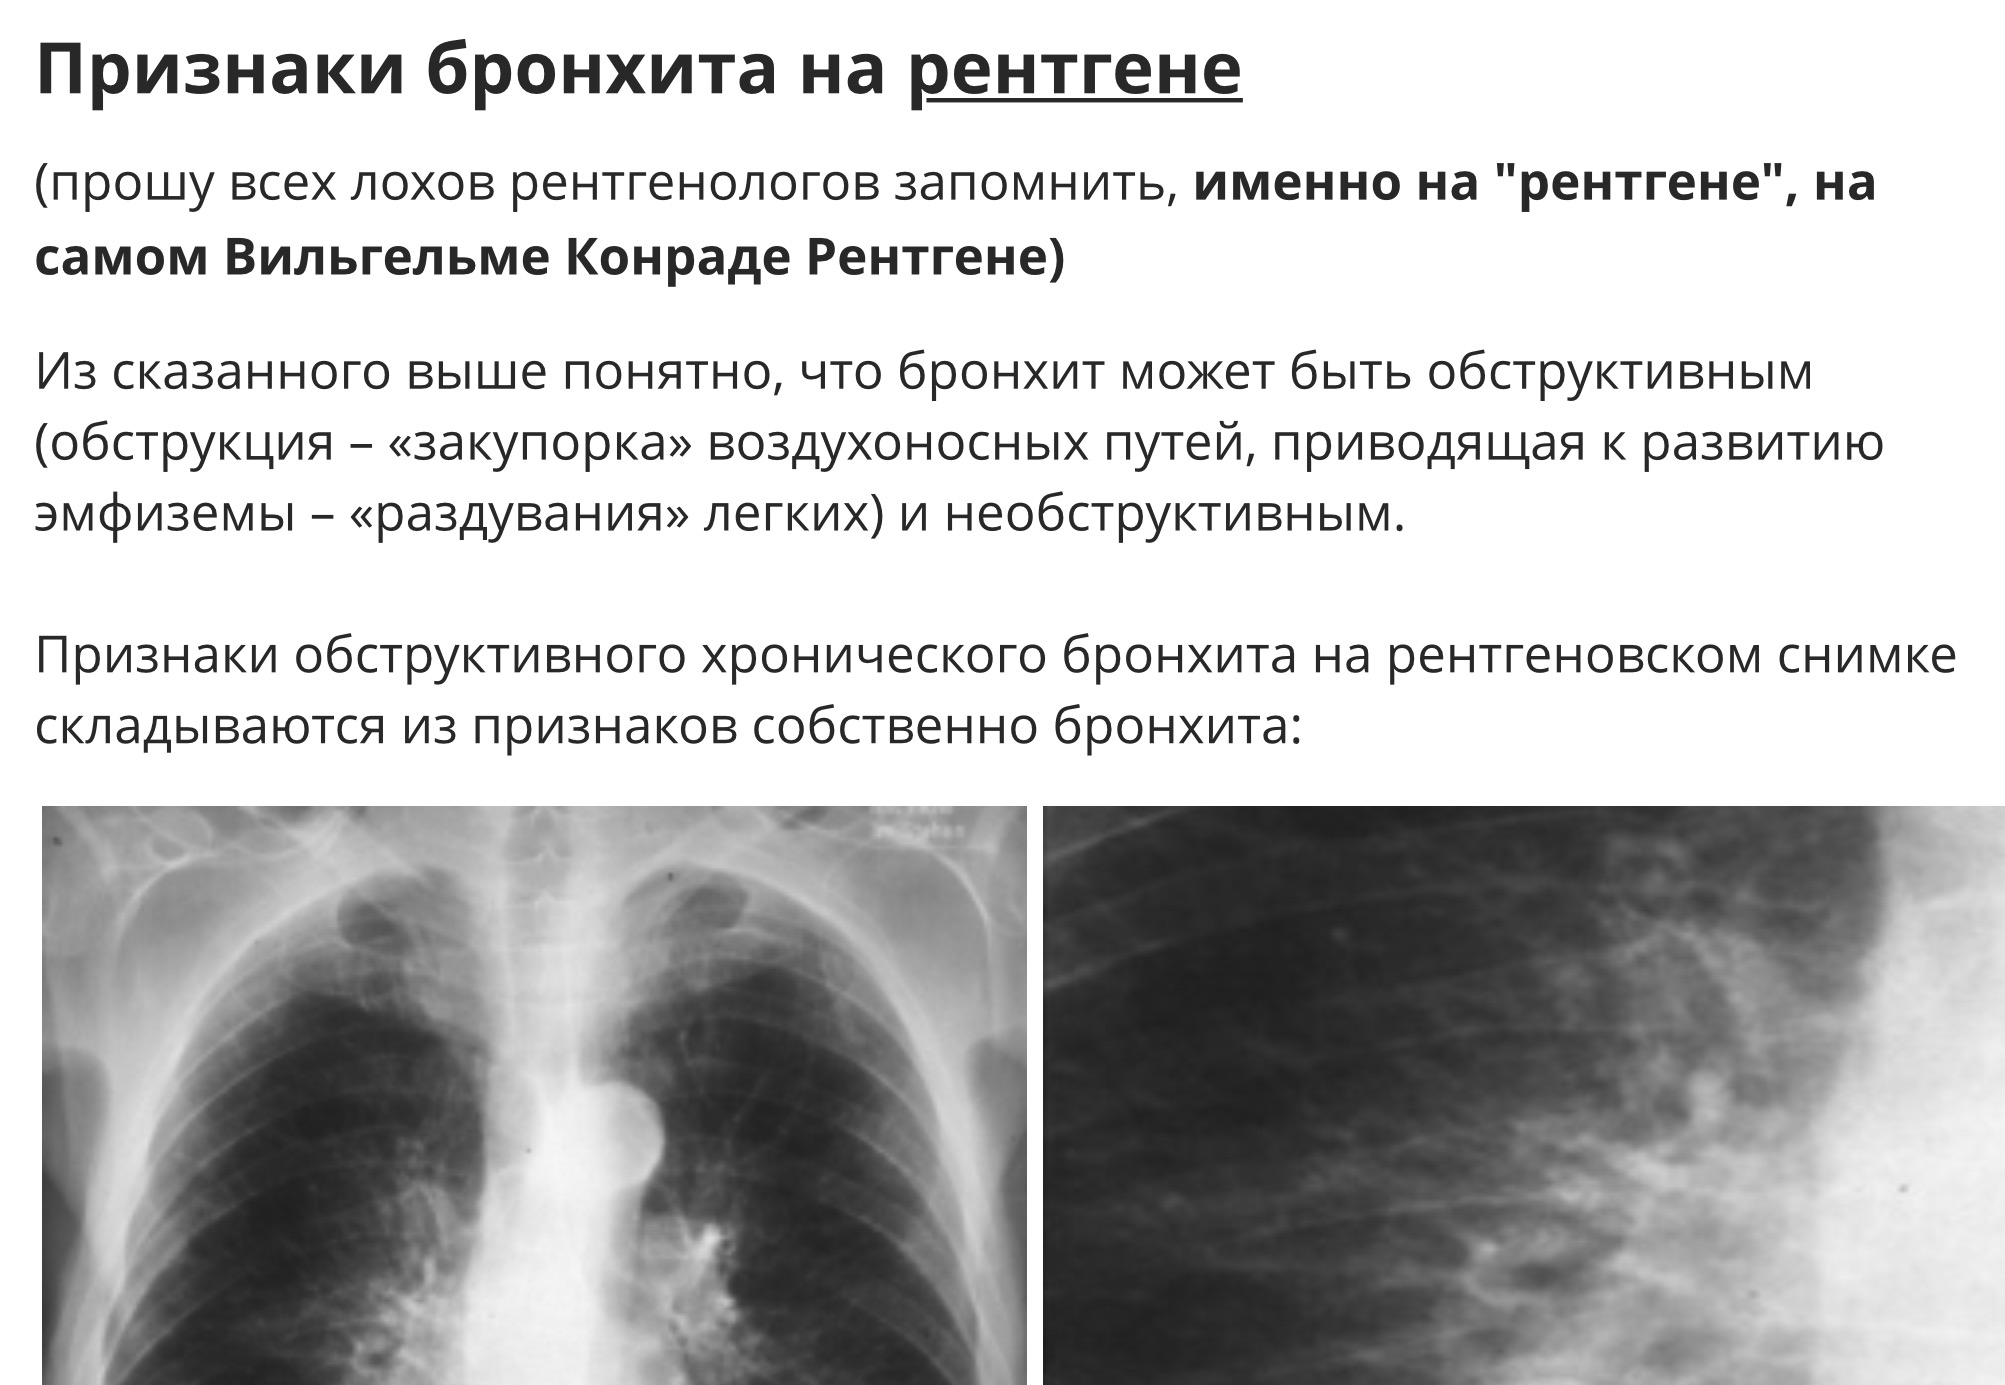

Рентгенодиагностика бронхопневмонии: Советы и примеры